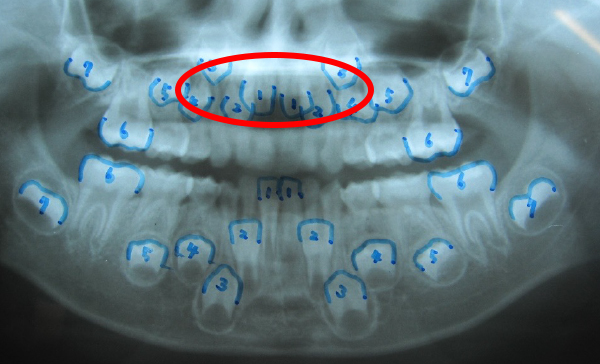

永久歯が生える前の矯正は①、永久歯が生えてからの矯正は②です。①の場合は、永久歯が生え変わる前に、全体的なレントゲンを撮影し、上下顎前歯4本が生え変わる場所があるか?どうかを診断します。歯並びが悪いお子さんの場合は、その場所がありません。

そのため、上下顎前歯部4本が生える場所を作る矯正になります。

赤丸の部分が、生える順序が違うようです。側切歯が早く、中切歯が遅い様です。

また、下顎前歯の永久歯幅が広く、生える場所が少ない様です。

智歯以外は、永久歯は全て存在しています。智歯に関しては、将来 出来てくる場合が有り、智歯の生え方や智歯の深さによりますが、矯正で動かない場合,又は、後戻りの原因になる場合は、大学での抜歯紹介も必要な場合があります。その時は、矯正による抜歯になりますので、自費治療になり、目安として、1本約15,000円必要になります。また、上顎の歯が、密集しており、上顎骨の劣成長(狭い成長)が考えられます。この事は、上顎骨劣成長→鼻腔狭窄→鼻閉→口呼吸習慣に至る傾向にあります。「いびき」・睡眠時無呼吸症候群・寝起きが悪い・中耳炎・夜尿症・などの原因になり易くなります。)通年、鼻づまりが、顎を拡げる事により改善する場合も多くあります。